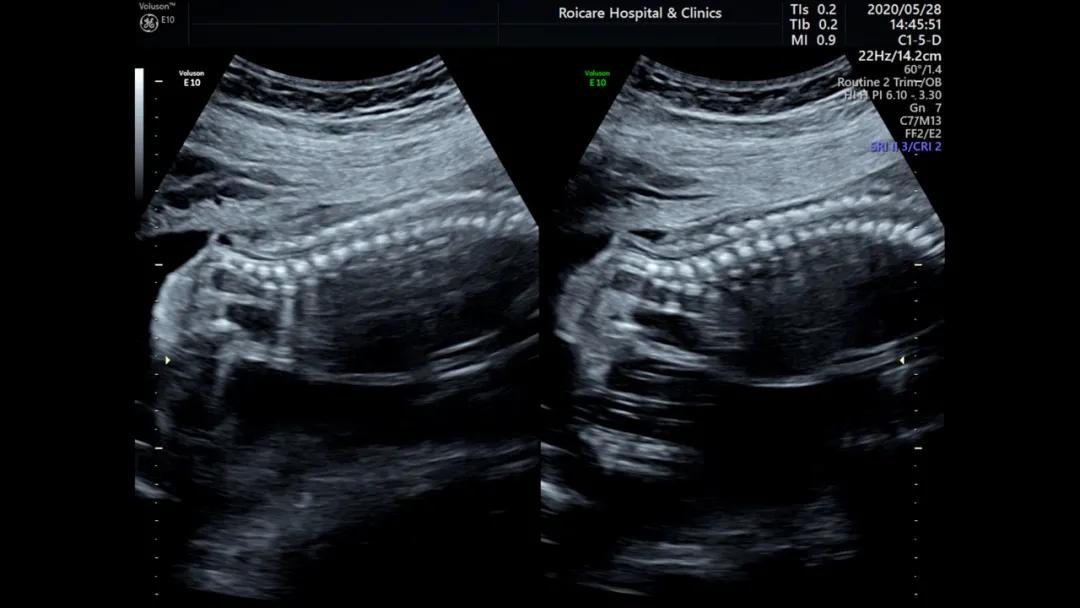

正常位置的脊髓圆锥

出生时脊髓圆锥位于第2腰椎(L2)至第3腰椎(L3)水平,出生后3个月位于L1~L2水平,与成人相同。脊髓下端因各种先天或后天原因受制于椎管的末端不能正常上升,使其位置低于正常,由此而导致的一系列临床神经功能障碍和畸形的综合征即称为脊髓拴系综合征。

正常孕20周以上的胎儿脊髓圆锥的位置达到L3水平以上,如果孕20周以上胎儿脊髓圆锥位置在L4以下,要警惕脊柱裂可能以及是否合并其他异常。中孕期产前超声检查可以发现严重的开放脊柱裂。闭合性脊柱裂表现多样、脊柱裂口小、影像学表现不典型,因此产前超声诊断困难。

脊髓圆锥低位

脊柱裂